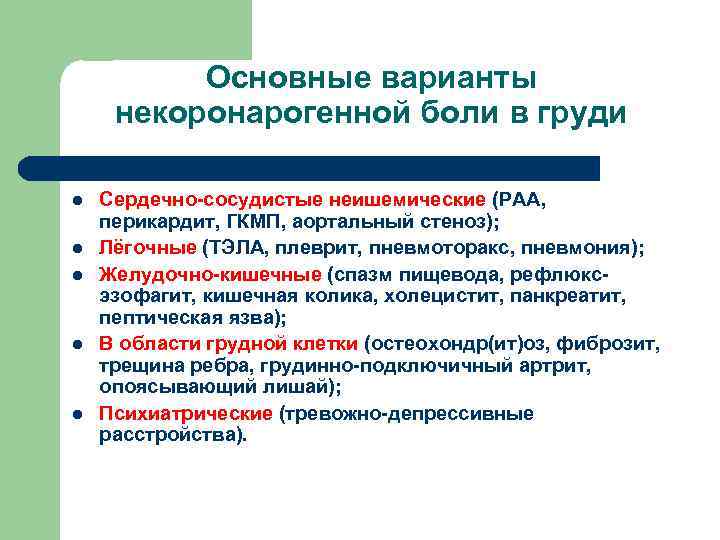

Основные варианты некоронарогенной боли в груди l l l Сердечно-сосудистые неишемические (РАА, перикардит, ГКМП, аортальный стеноз); Лёгочные (ТЭЛА, плеврит, пневмоторакс, пневмония); Желудочно-кишечные (спазм пищевода, рефлюксэзофагит, кишечная колика, холецистит, панкреатит, пептическая язва); В области грудной клетки (остеохондр(ит)оз, фиброзит, трещина ребра, грудинно-подключичный артрит, опоясывающий лишай); Психиатрические (тревожно-депрессивные расстройства).